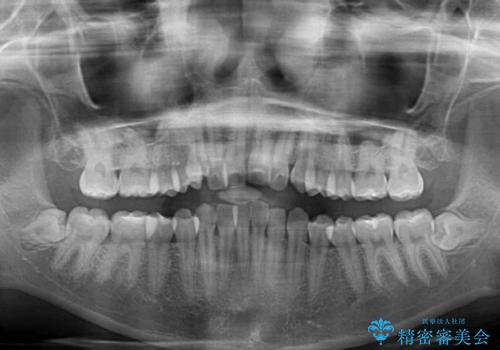

- 上顎の八重歯と、上下前歯のデコボコを気にして来院された患者様です。

奥歯の咬み合わせを見ると、上顎臼歯が下顎に対して前方にあり、叢生改善により口元が突出する顔貌ではなかったため、上顎左右第一小臼歯2本を抜歯し、ワイヤー装置にて矯正治療を行うこととしました。